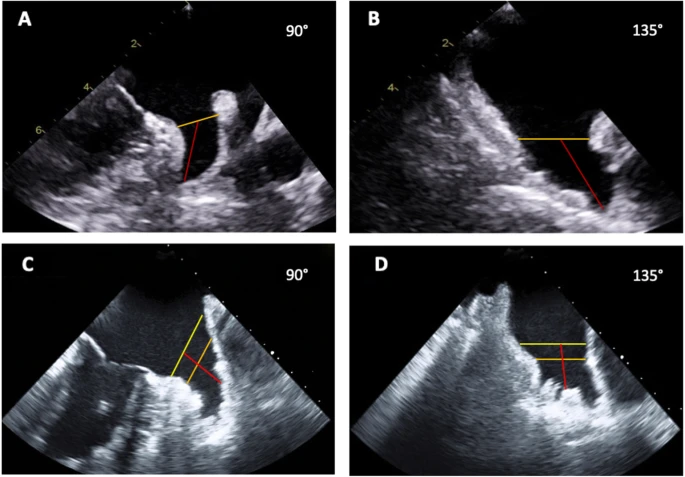

Radiology Case Reports

Left ventricular pseudoaneurysm: An unexpected finding